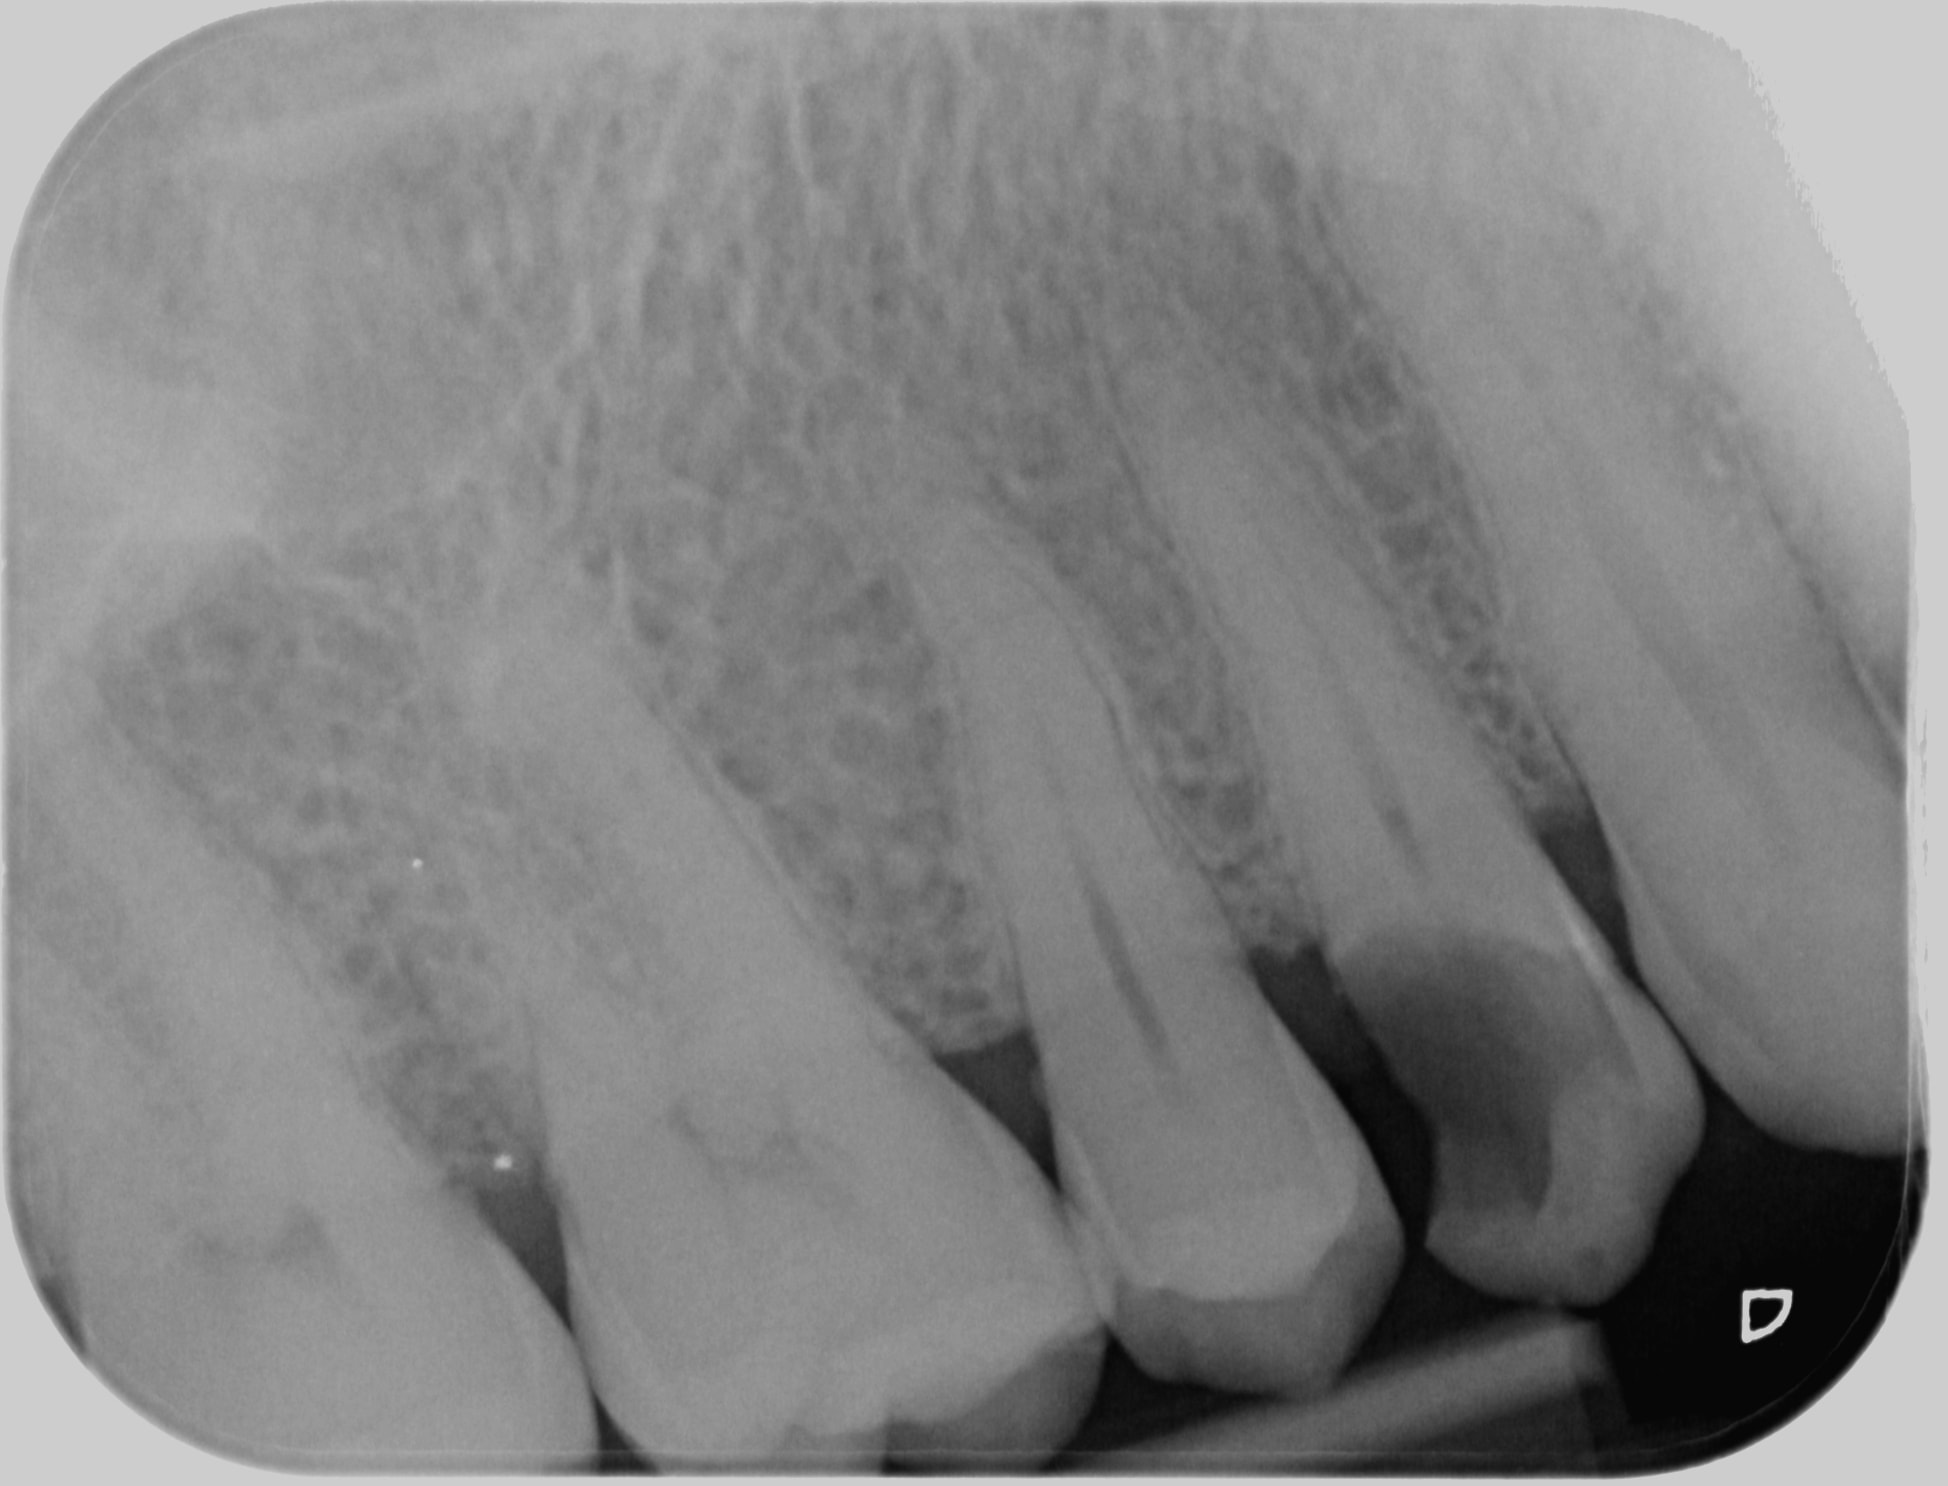

1er rdv 40min endo taille empreinte clip voco (je sais pas si je pourrais le coter 25e en janvier mais pourquoi pas?)

2nd rdv 20min pose de la chinoiserie (ic+ccm 90e...)

Honoraires: 48.20 endos + 15.96 radio + 2x28.92 det (lol) + 129.80 IC + 410e de ccm

662e d'honoraires, 90e de frais de prothèse, 1h de travail. Bienvenue dans le RA.

1513 x 20171006 172319 x9hxynwtya8k 4 wofe6p - Eugenol

1513 x 20170908 152454 x3droyelajju 4 da6flu - Eugenol

20171006 202552 p5wrww - Eugenol

20171006 202647 c5rk4d - Eugenol

Tres tres propre du debut à la fin , cette chinoiserie Hoku .